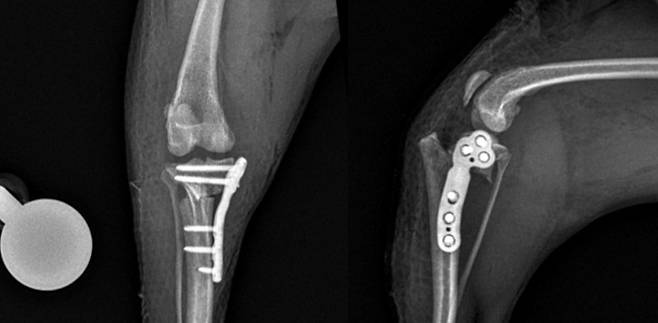

치료법 중 하나로 뼈의 각도를 조절해 관절의 안정성을 되찾아주는 TPLO 수술이 있다. 노령견을 대상으로 하는 고난도 정형외과 수술로 마취의 안전성과 수술 전후의 통증 관리, 수술 계획에 따라 환자의 예후가 중요하다.

예은동물의료센터는 1일 평균 3건 이상의 TPLO 수술을 한다. 특히 노령견에 특화된 TPLO 수술 및 마취 시스템을 구축해 이에 맞는 진료를 하고 있다.

임플란트도 반려동물 맞춤형으로 적용된다. 최신 기구를 환견의 체구에 맞게 종류별, 크기별로 구비해 초소형견부터 대형견까지 최적의 수술을 한다.